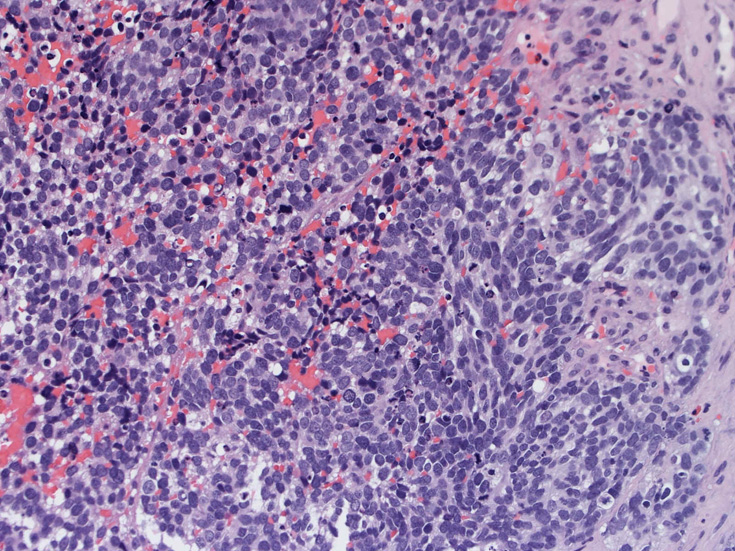

30歳代男性 鼻腔腫瘤の生検組織

厳密にはalveolar patternが明らかではなく, solid typeに入る症例かもしれない。異型細胞増殖胞巣が線維化組織に取り囲まれるように散在している. 小さな生検組織のため全体像が不明である。

鼻腔腫瘤生検組織